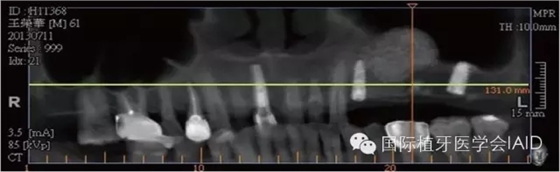

在植牙手術(shù)執(zhí)行之前,需要進(jìn)行全口檢查與軟硬組織的評(píng)估。口外石膏模型與cone beam CT資料搜集有助于治療計(jì)劃的擬定。在石膏模型上進(jìn)行diagnostic wax up有助于決定植體上假牙前后關(guān)系、頰舌側(cè)位置、咬合高度、及植體與植體上假牙的高度比例。使用Cone beam CT(CBCT)可以容易了解手術(shù)區(qū)硬組織條件,如Septum、骨頭高度及寬度、骨頭密度、神經(jīng)血管位置等。分析以上數(shù)據(jù)后,較容易得到可預(yù)期性的結(jié)果。

初期穩(wěn)定度在第一及第二類型的案例(>9mm; 6mm-9mm) 可以較容易達(dá)到,故通常以crestal approach進(jìn)行手術(shù)。Lateral window術(shù)式在第三型(3mm-6mm)較被建議。 若是前三個(gè)類型的初期穩(wěn)定度達(dá)到35Mpa,可以考慮當(dāng)次放置植體。若骨頭條件屬于第四型(<3mm),Lateral approach 比較建議使用,而植體可考慮等到Grafted Bone較成熟時(shí)再置入。(Fig. 1 & 2)術(shù)式的選擇與骨頭高度有密切的關(guān)系,當(dāng)骨頭垂直高度小于3 mm(于兩顆植體中),植體應(yīng)考慮 Bone graft穩(wěn)定后再植入。